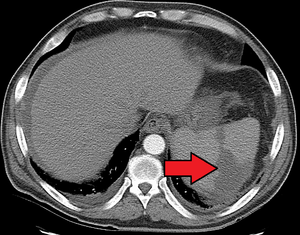

Splenic infarction is a condition in which oxygen supply to the spleen is interrupted, leading to partial or complete infarction (tissue death due to oxygen shortage) in the organ.[1]

Splenic infarction occurs when the splenic artery or one of its branches are occluded, for example by a blood clot. Although it can occur asymptomatically, the typical symptom is severe pain in the left upper quadrant of the abdomen, sometimes radiating to the left shoulder. Fever and chills develop in some cases.[2] It has to be differentiated from other causes of acute abdomen.

An abdominal CT scan is the most commonly used modality to confirm the diagnosis,[2] although abdominal ultrasound can also contribute.[3][4][5]